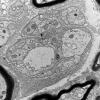

3B3 (Case 3) 015 - Copy

3B3 AIN_012 - Copy

3B3 AMPK KO Mouse Degen Axons_026.jpg

3B3 Axonal Degeneration (Case 4) EM 086 copy - Copy

3B3 Axonal regeneration, SLE NP Vasculitis (Case 1)_003 - Copy

3B3 Diabetes longitudinal, SLC (Case 3) 016 - Copy copy

3B3 Dmyel, remyel & AD (Case 3) EM 070 copy - Copy - Copy

3B3 Sarcoid (Case 3) Plastic 13